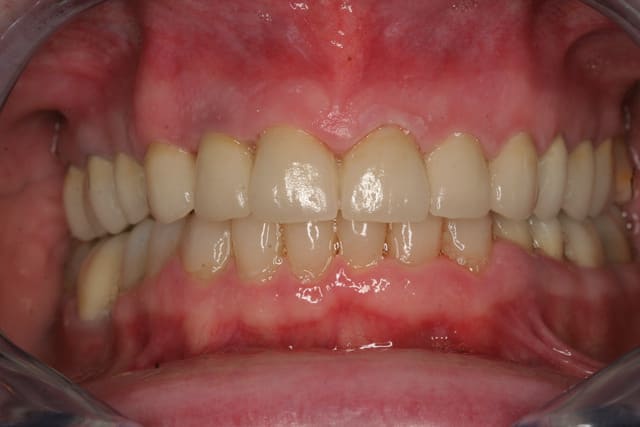

Et voila la pose , pour les habitants du nouveau monde c'est très coloré, pour les Franchouillard c'est naturel... perso je m'en fout la patiente est toute joilleuse et j'ai pas honte de moi, j'ferais encore mieux dés qu'on m'en donneras l'occasion.

Merci de m'avoir laisser finir sans me tailler un short tout de suite!